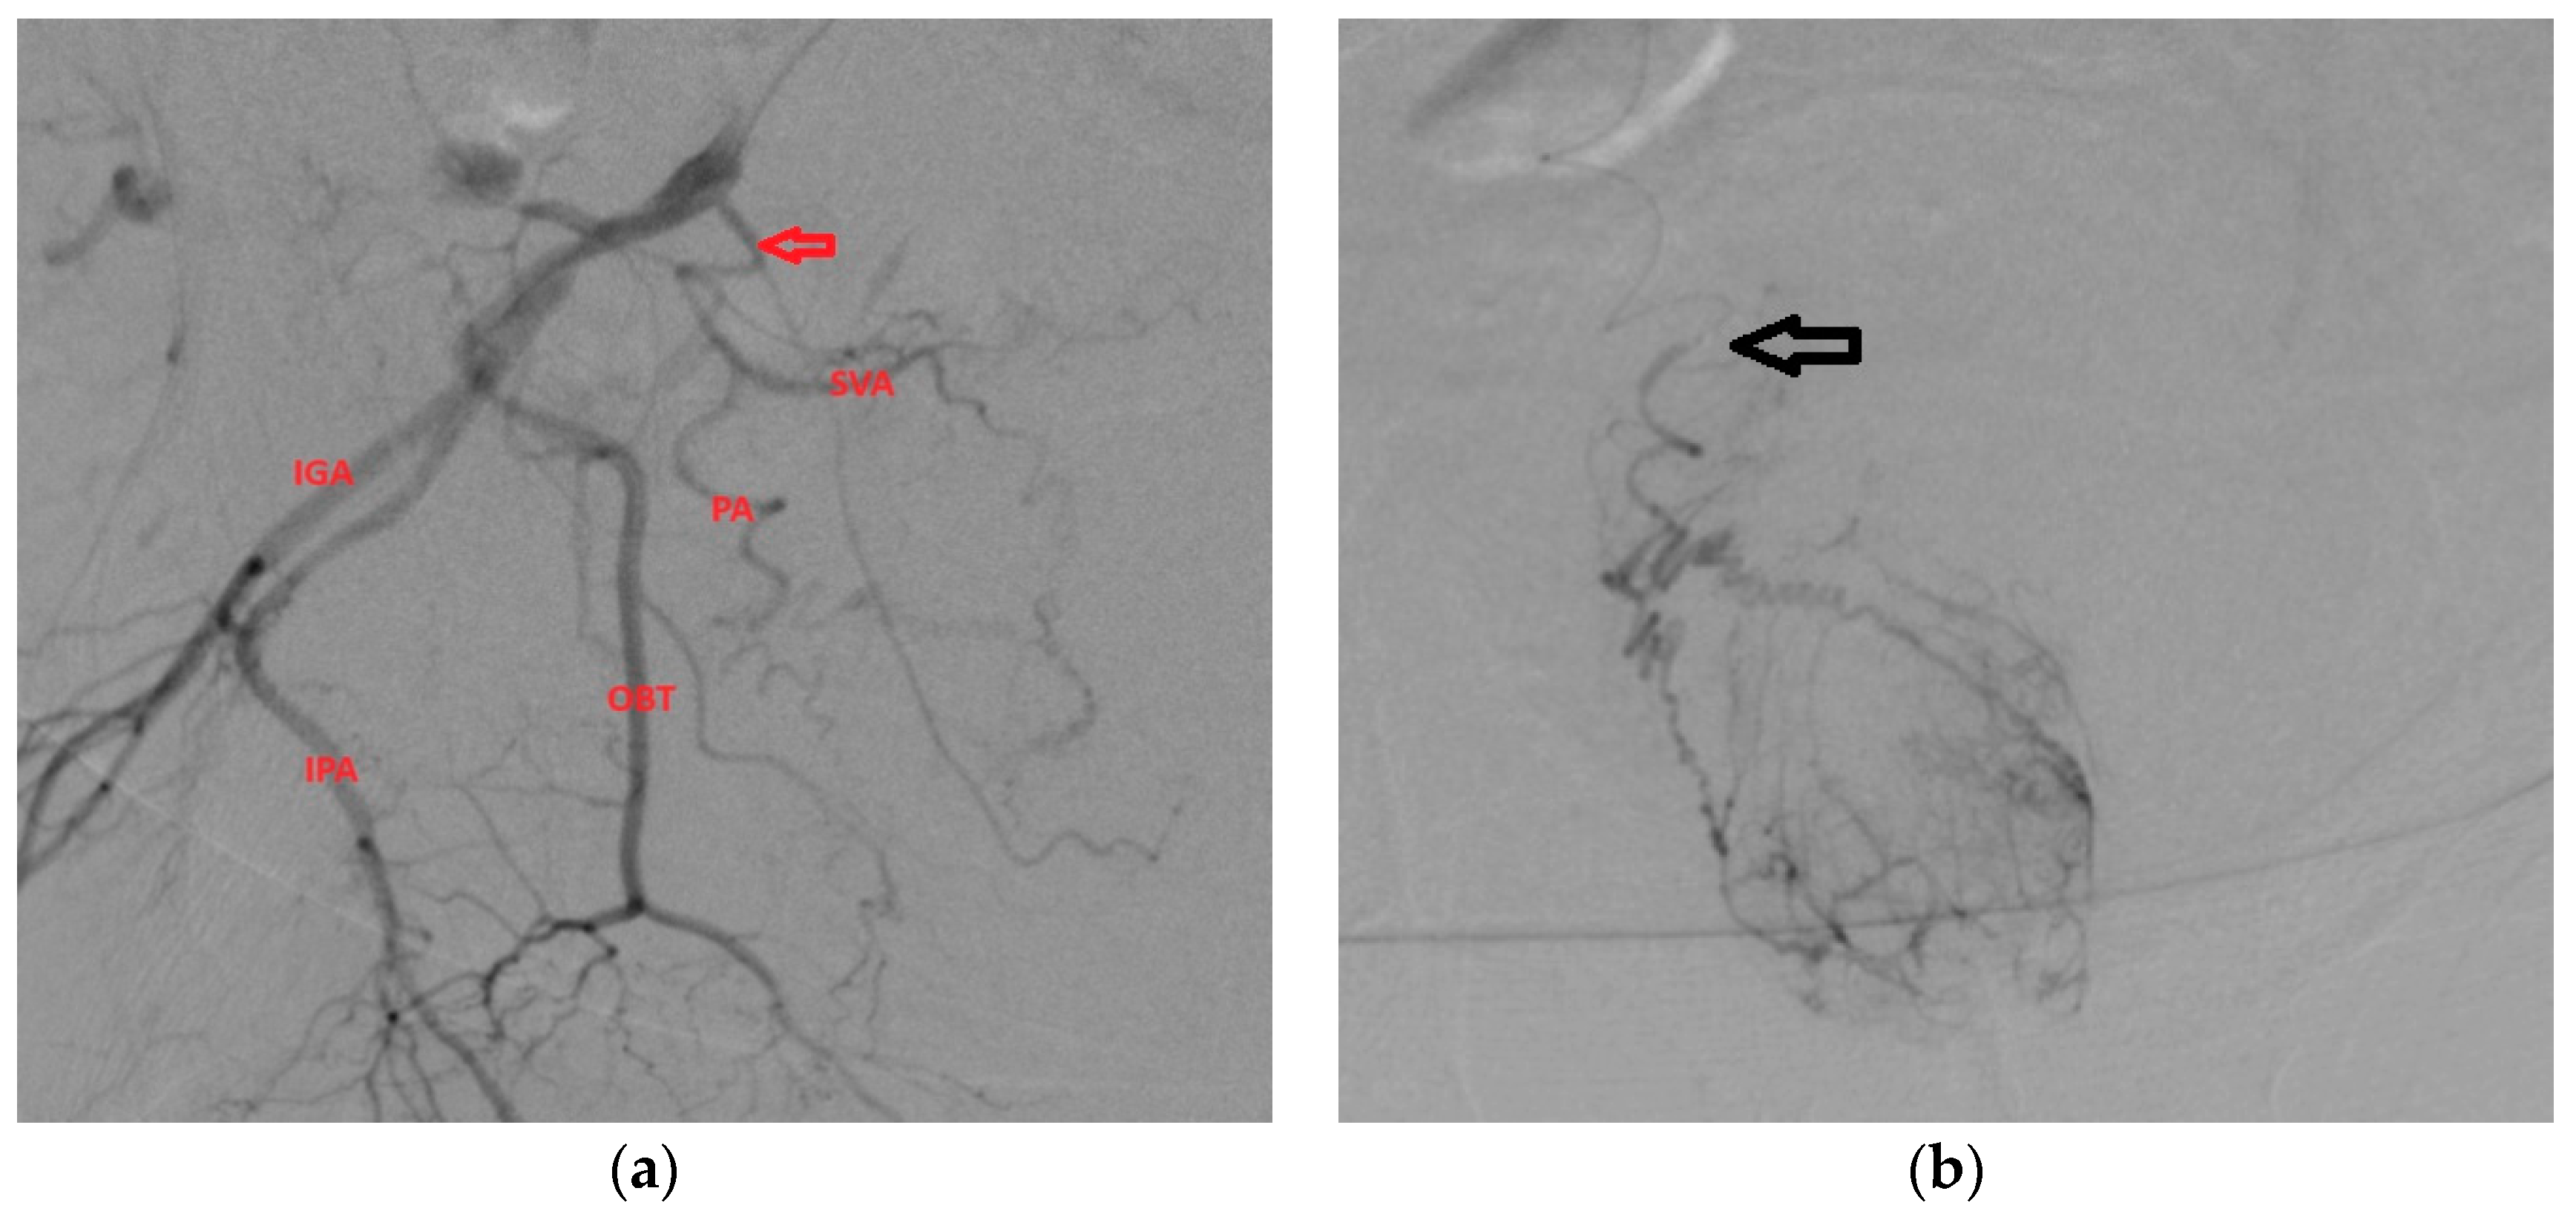

- After we identified the four main branches (superior gluteal artery, inferior gluteal artery, obturator artery, internal pudendal artery), we searched for the PA artery, which usually has a characteristic corkscrew aspect and parallel trajectory with the IPA.

- There are cases when we can identify IPA and IPA accessories, which must not be confused with the PA. At the level of accessory IPAs, we can find the origin of the middle rectal artery, which has a characteristic pattern of enhancement that cannot be mistaken with the prostatic blush [12] (Figure 2);

3.1.2. PA with Origin from Anterior Gluteal Trunk

3.1.3. PA with Origin from SVA

3.2.1. PA origin with Common Trunk

3.2.2. Anastomoses of PA with Penile Artery

3.2.3. Middle Rectal Artery with Origin from PA